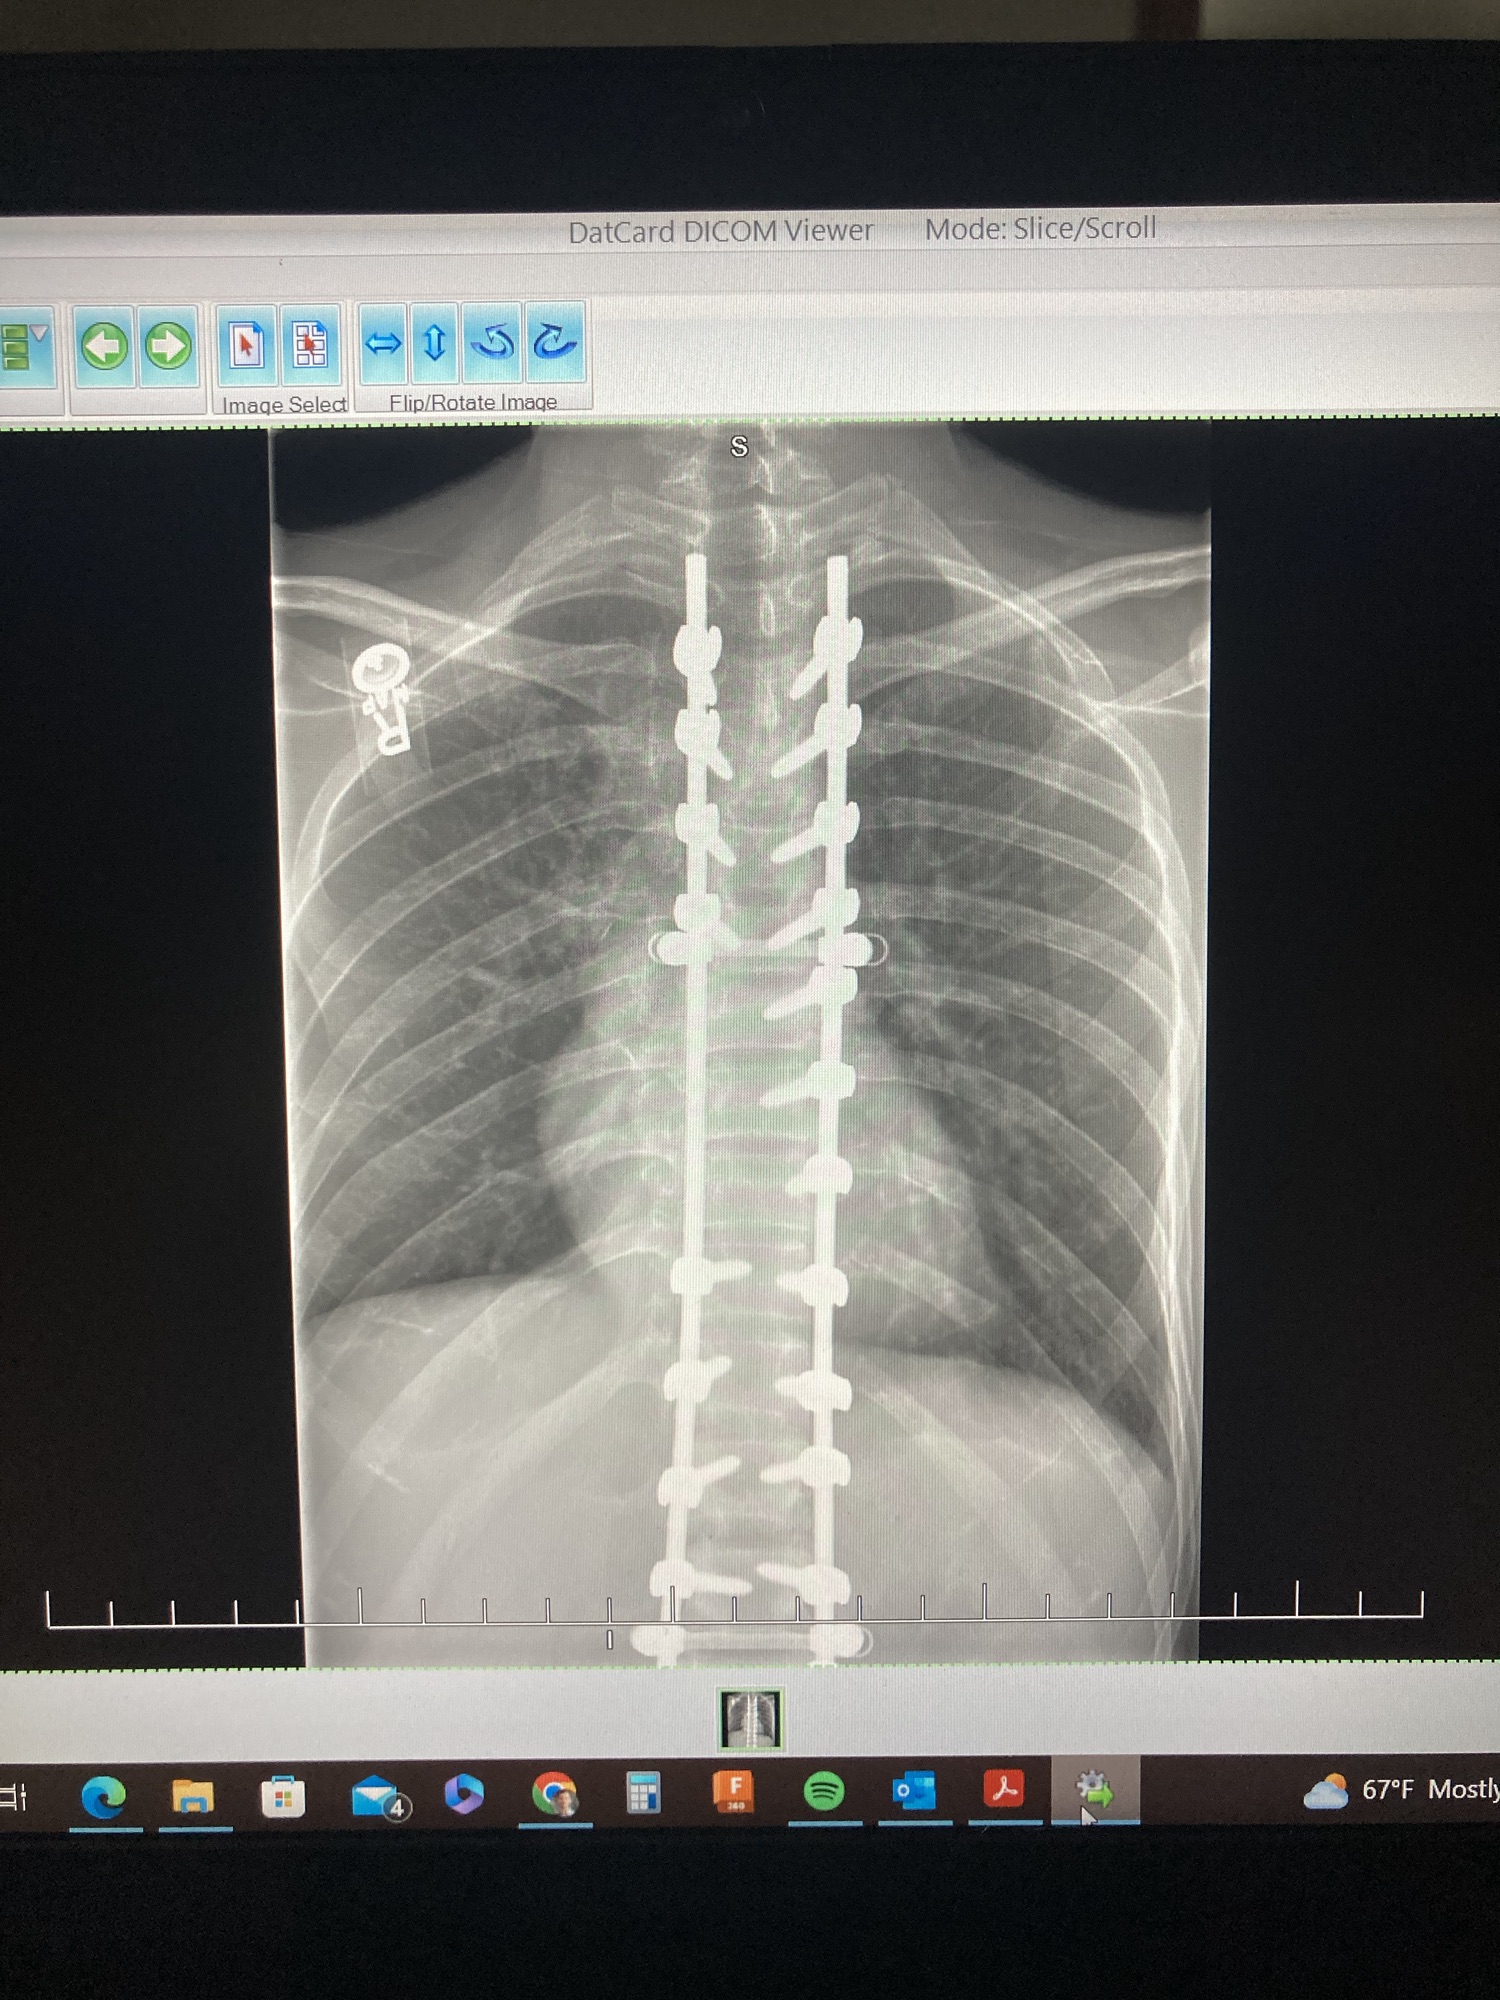

The Astronaut on Earth is the story of a man with an incredible family, navigating life after a spinal cord injury.

It’s about reclaiming his body, identity, and movement — one breath, one day, one breakthrough at a time.

Framed through the lens of an astronaut learning to survive in zero gravity, this is a mission to relearn everything:

how to breathe, eat, sleep, shower, exercise, use the bathroom, and eventually… walk again.